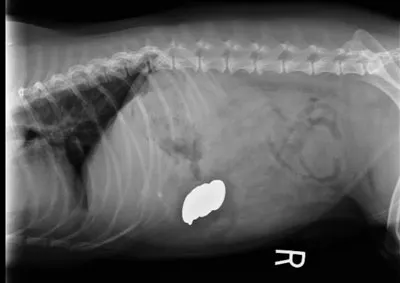

Abdominal radiography revealed metallic foreign bodies (Figure 2) in the stomach. Multiple coins, including some zinc containing pennies minted after 1982, and a medallion were removed endoscopically (Figure 3). Blood zinc levels were not measured.

Lateral abdominal radiograph revealing metallic foreign bodies